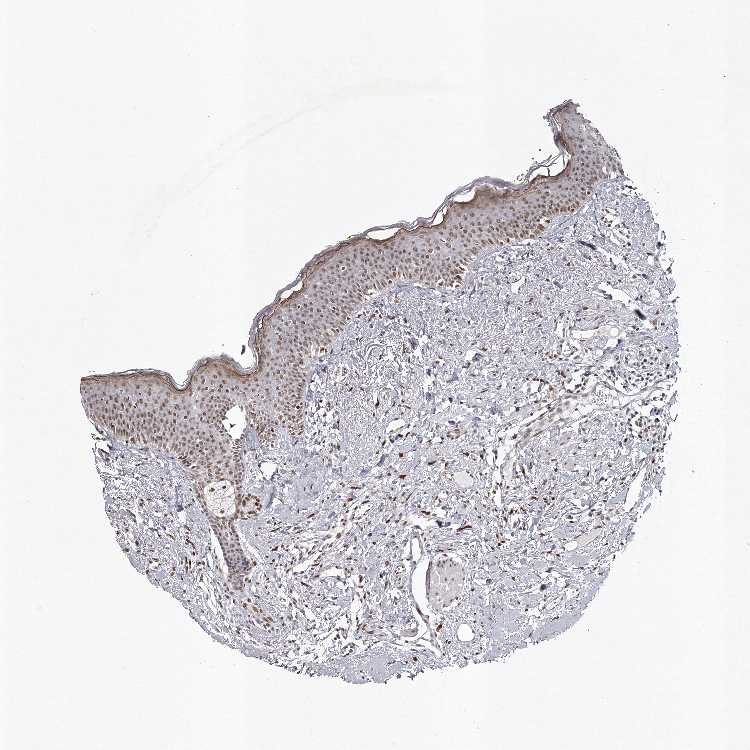

TISSUE PRIMARY DATA ORAL MUCOSA Show tissue menu

Oral mucosa

ORAL MUCOSA - Antibody stainingi

Antibody staining in the annotated cell types in the current human tissue is reported as not detected, low, medium, or high, based on conventional immunohistochemistry profiling in selected tissues. This score is based on the combination of the staining intensity and fraction of stained cells.

Each image is clickable and will lead to virtual microscopy that enables deeper exploration of all samples and also displays staining intensity scores, fraction scores and subcellular localization as well as patient and tissue information for each sample.

Antibody HPA038904

Squamous epithelial cells Medium